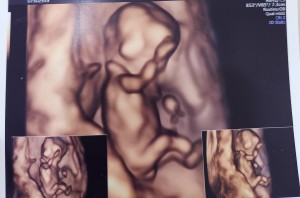

갑자기 쌍둥이..

닉네임_김*아_83

2025-04-16

13